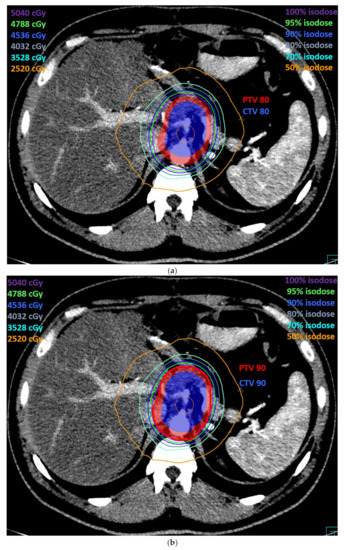

3. Results

4. Discussion